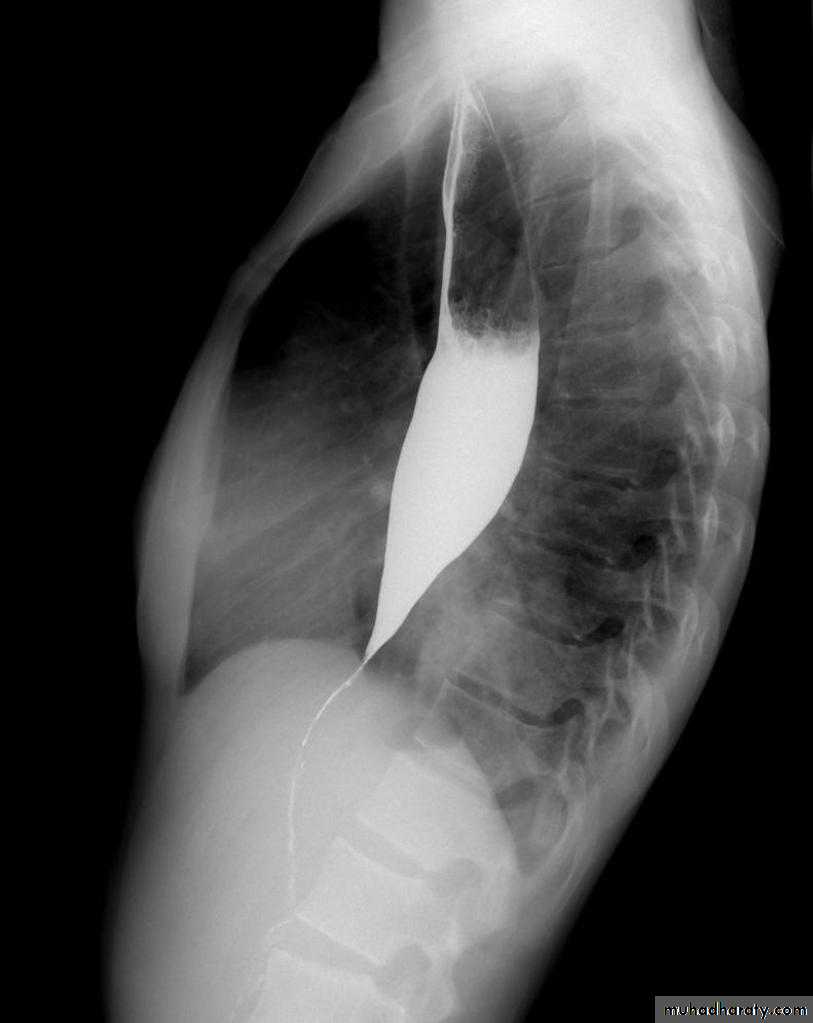

• Dilatation: obstructive vs. non-obstructive

Stricture

Benign vs. malignant Causes Specific locationContrast study EUS CT